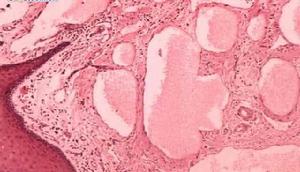

組織病理示毛細淋巴管瘤由襯有內皮細胞的微小淋巴管擴張而成,內含淋巴液,位於真皮上部,表皮可萎縮或增生。